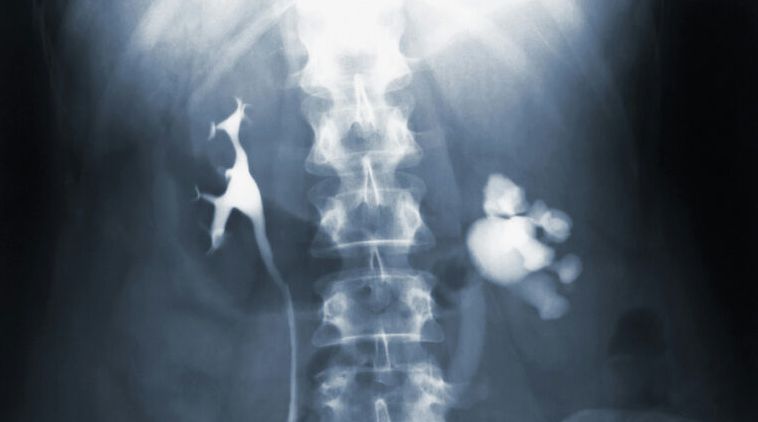

Минздрав Новосибирской области уточнил, что методы диагностики и лечения для детей и взрослых отличаются, и основным методом раннего выявления инфекции является систематическая иммунодиагностика: дети до 7 лет проходят пробу Манту, с 8 лет – Диаскинтест, а подростки с 15 лет – Диаскинтест и флюорографию. Туберкулез – инфекционное заболевание, поражающее преимущественно легкие, но может затрагивать и другие органы.